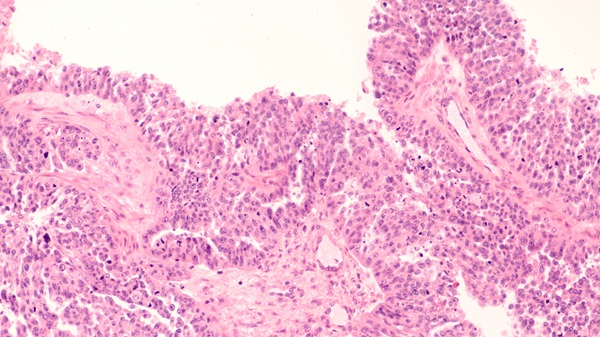

Imagen: Los frotis de aspirado de médula ósea de un paciente con leucemia linfoide aguda revela un aumento de blastos de tamaño pequeño a mediano con una alta relación núcleo-citoplasma, núcleos redondos a irregulares, cromatina lisa y escaso citoplasma agranular basófilo (Fotografía cortesía de Karen M. Chisholm MD, PhD).